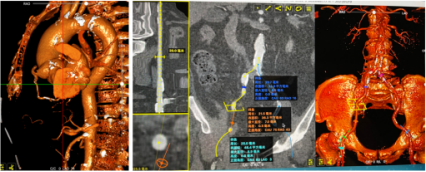

冠脉造影

导丝跨瓣

球囊预扩

瓣膜初始定位

完全释放,瓣膜形态良好,无周漏

在陈玉国院长带领下,山东大学齐鲁医院急诊科取得了该例手术的圆满成功。术后,患者跨瓣压差由术前的63mmHg降至术后8mmHg,无反流及瓣周漏。